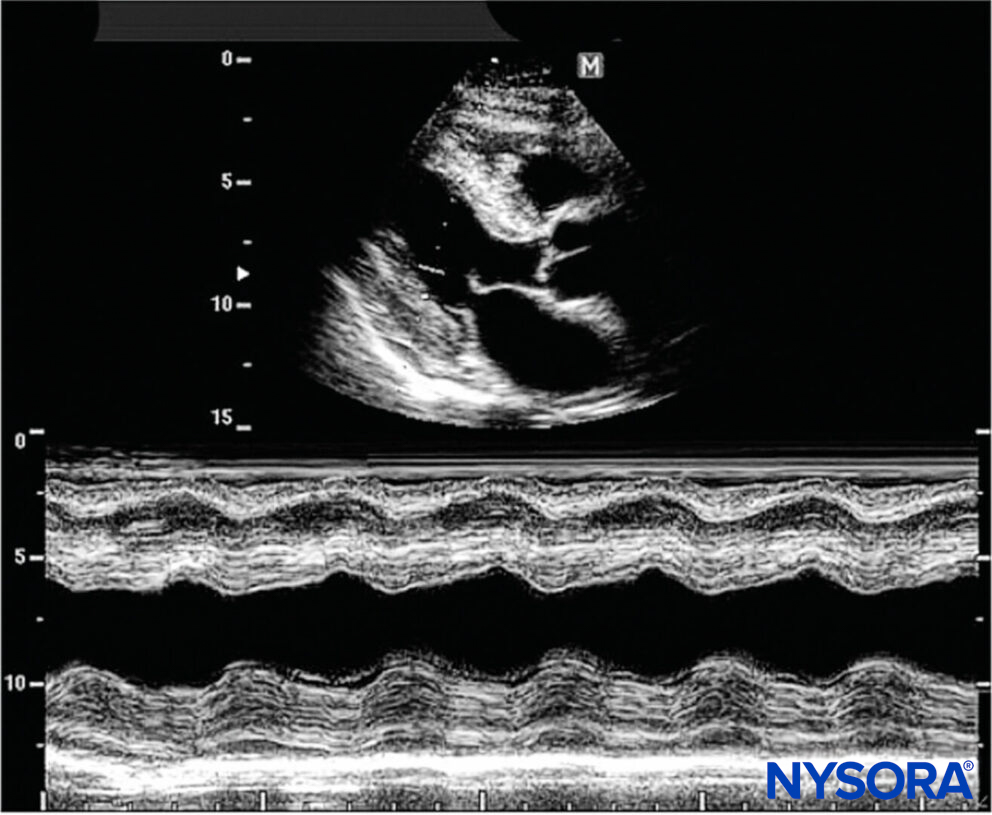

M-mode

A single beam in an ultrasound scan can be plotted in function of time. This produces a picture with a motion signal, in which the movement of a structure, such as a heart valve, can be depicted as a wave. M-mode is used extensively in cardiac and fetal cardiac imaging.

M-mode: The vertical structure is the image plane, while the horizontal is time.